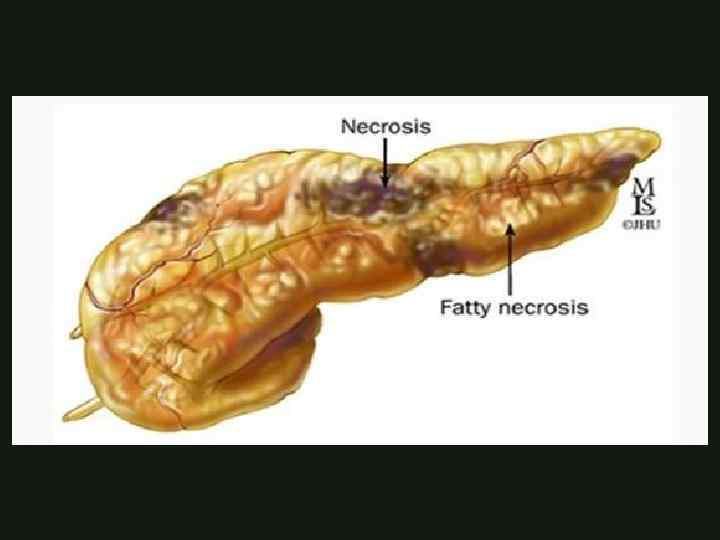

КЛАССИФИКАЦИЯ ОСТРОГО ПАНКРЕАТИТА Осложнения острого тяжёлого Панкреатита Панкреатический некроз - диффузная или локальная зона (зоны) нежизнеспособной паренхимы, которая, как правило, сопровождается перипанкреатическим жировым некрозом. КАФЕДРА ХИРУРГИИ МОСКОВСКОГО ФАКУЛЬТЕТА

КЛАССИФИКАЦИЯ ОСТРОГО ПАНКРЕАТИТА Осложнения острого тяжёлого Панкреатита Панкреатический некроз - диффузная или локальная зона (зоны) нежизнеспособной паренхимы, которая, как правило, сопровождается перипанкреатическим жировым некрозом. КАФЕДРА ХИРУРГИИ МОСКОВСКОГО ФАКУЛЬТЕТА